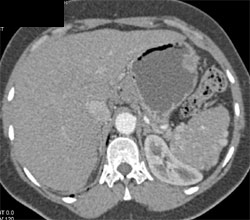

Accessory Spleens